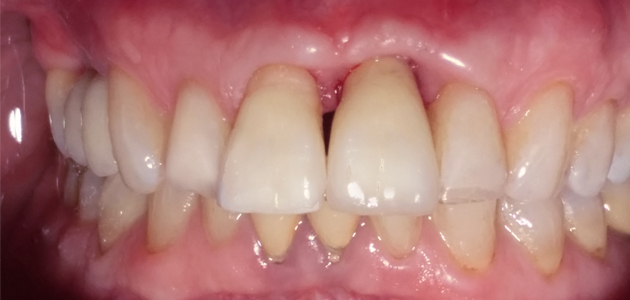

Situation clinique initiale avant traitement

En raison de problèmes de rhizalyse, une résorption pathologique de la racine, ainsi que d’une infection, l’incisive centrale du patient a été extraite.